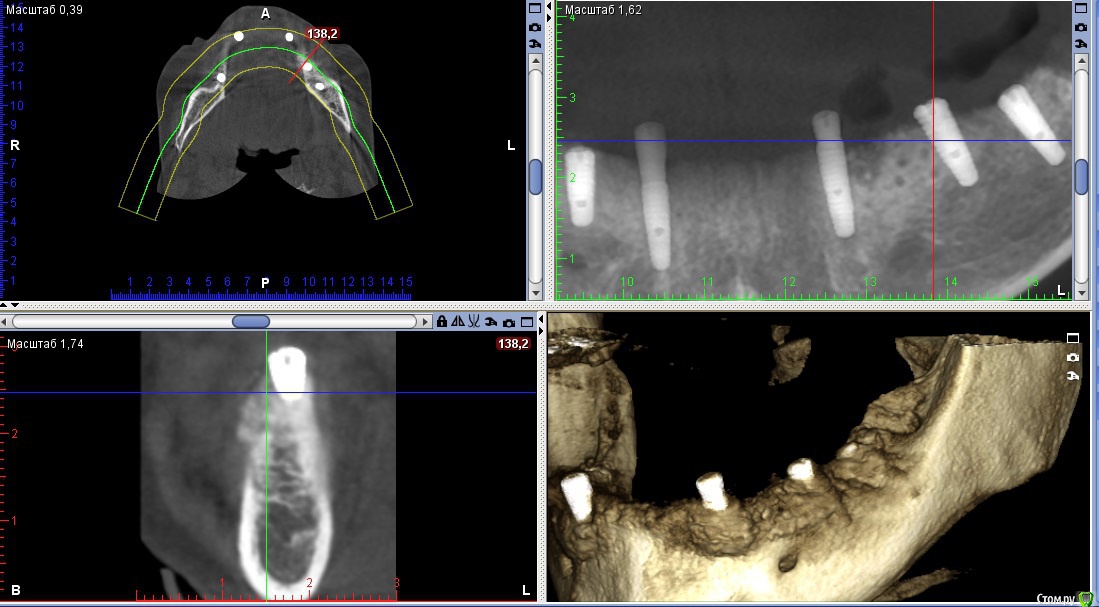

Nitrino1 Опубликовано 21 февраля, 2018 Автор Поделиться Опубликовано 21 февраля, 2018 Коллеги, сделали КТ, картина следующая. Вопрос, как рекомендуете, переустановить на то же самое место только глубже или же все таки менять место?ССТ все таки рекомендуете сделать:? Ссылка на комментарий

dok1 Опубликовано 22 февраля, 2018 Поделиться Опубликовано 22 февраля, 2018 Я бы в таких случаях расщеплялся и заглублялся. И импланты не толще 3.5 мм. Потом после интеграции "шашлычок". Ссылка на комментарий